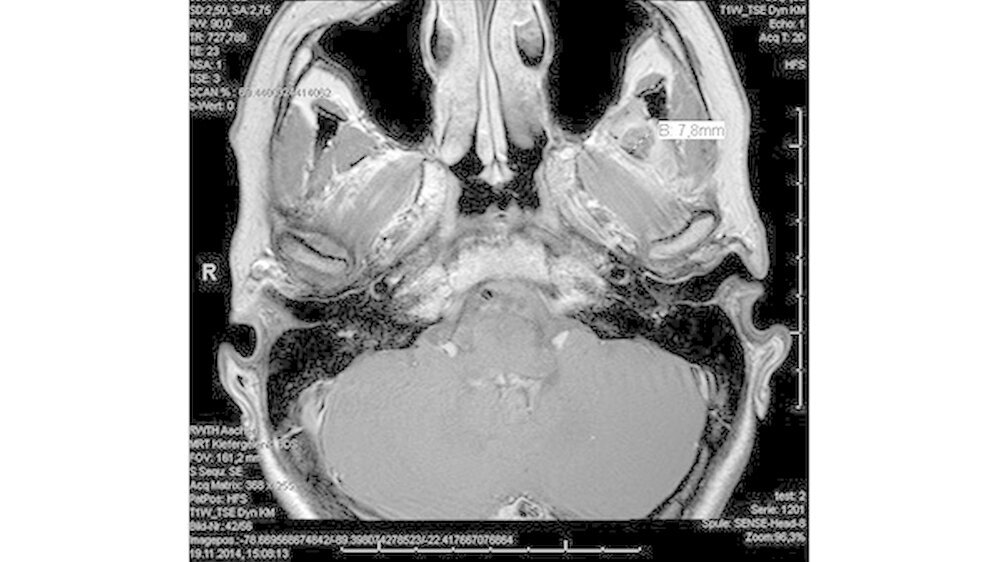

Klinisch waren extraoral keine Schwellung oder Rötung im Bereich des Kiefergelenks links erkennbar. Die lokoregionalen Lymphknoten waren nicht vergrößert. Es bestand eine Kieferklemme mit etwa 8mm Schneidekantendistanz (Abbildung 2) und das linke Kiefergelenk war bei direkter Krafteinwirkung leicht druckdolent. Enoral waren die sichtbaren Mundschleimhäute blass rosa, ebenfalls ohne Anhalt auf eine Schwellung oder Entzündung.

Das neun Tage später durchgeführte MRT zeigte keinen Anhalt für eine Läsion des Diskuskomplexes beidseits. Es wurde jedoch eine umschriebene, teils T2-hyperintense sowie kräftig randständig kontrastmittelaufnehmende Läsion im M. pterygoideus medialis links (axial bis zirka 1,0 cm) angrenzend an den Processus muscularis vereinbar mit einem kleinen intramuskulären Abszess beschrieben (Abbildungen 3 a und b).